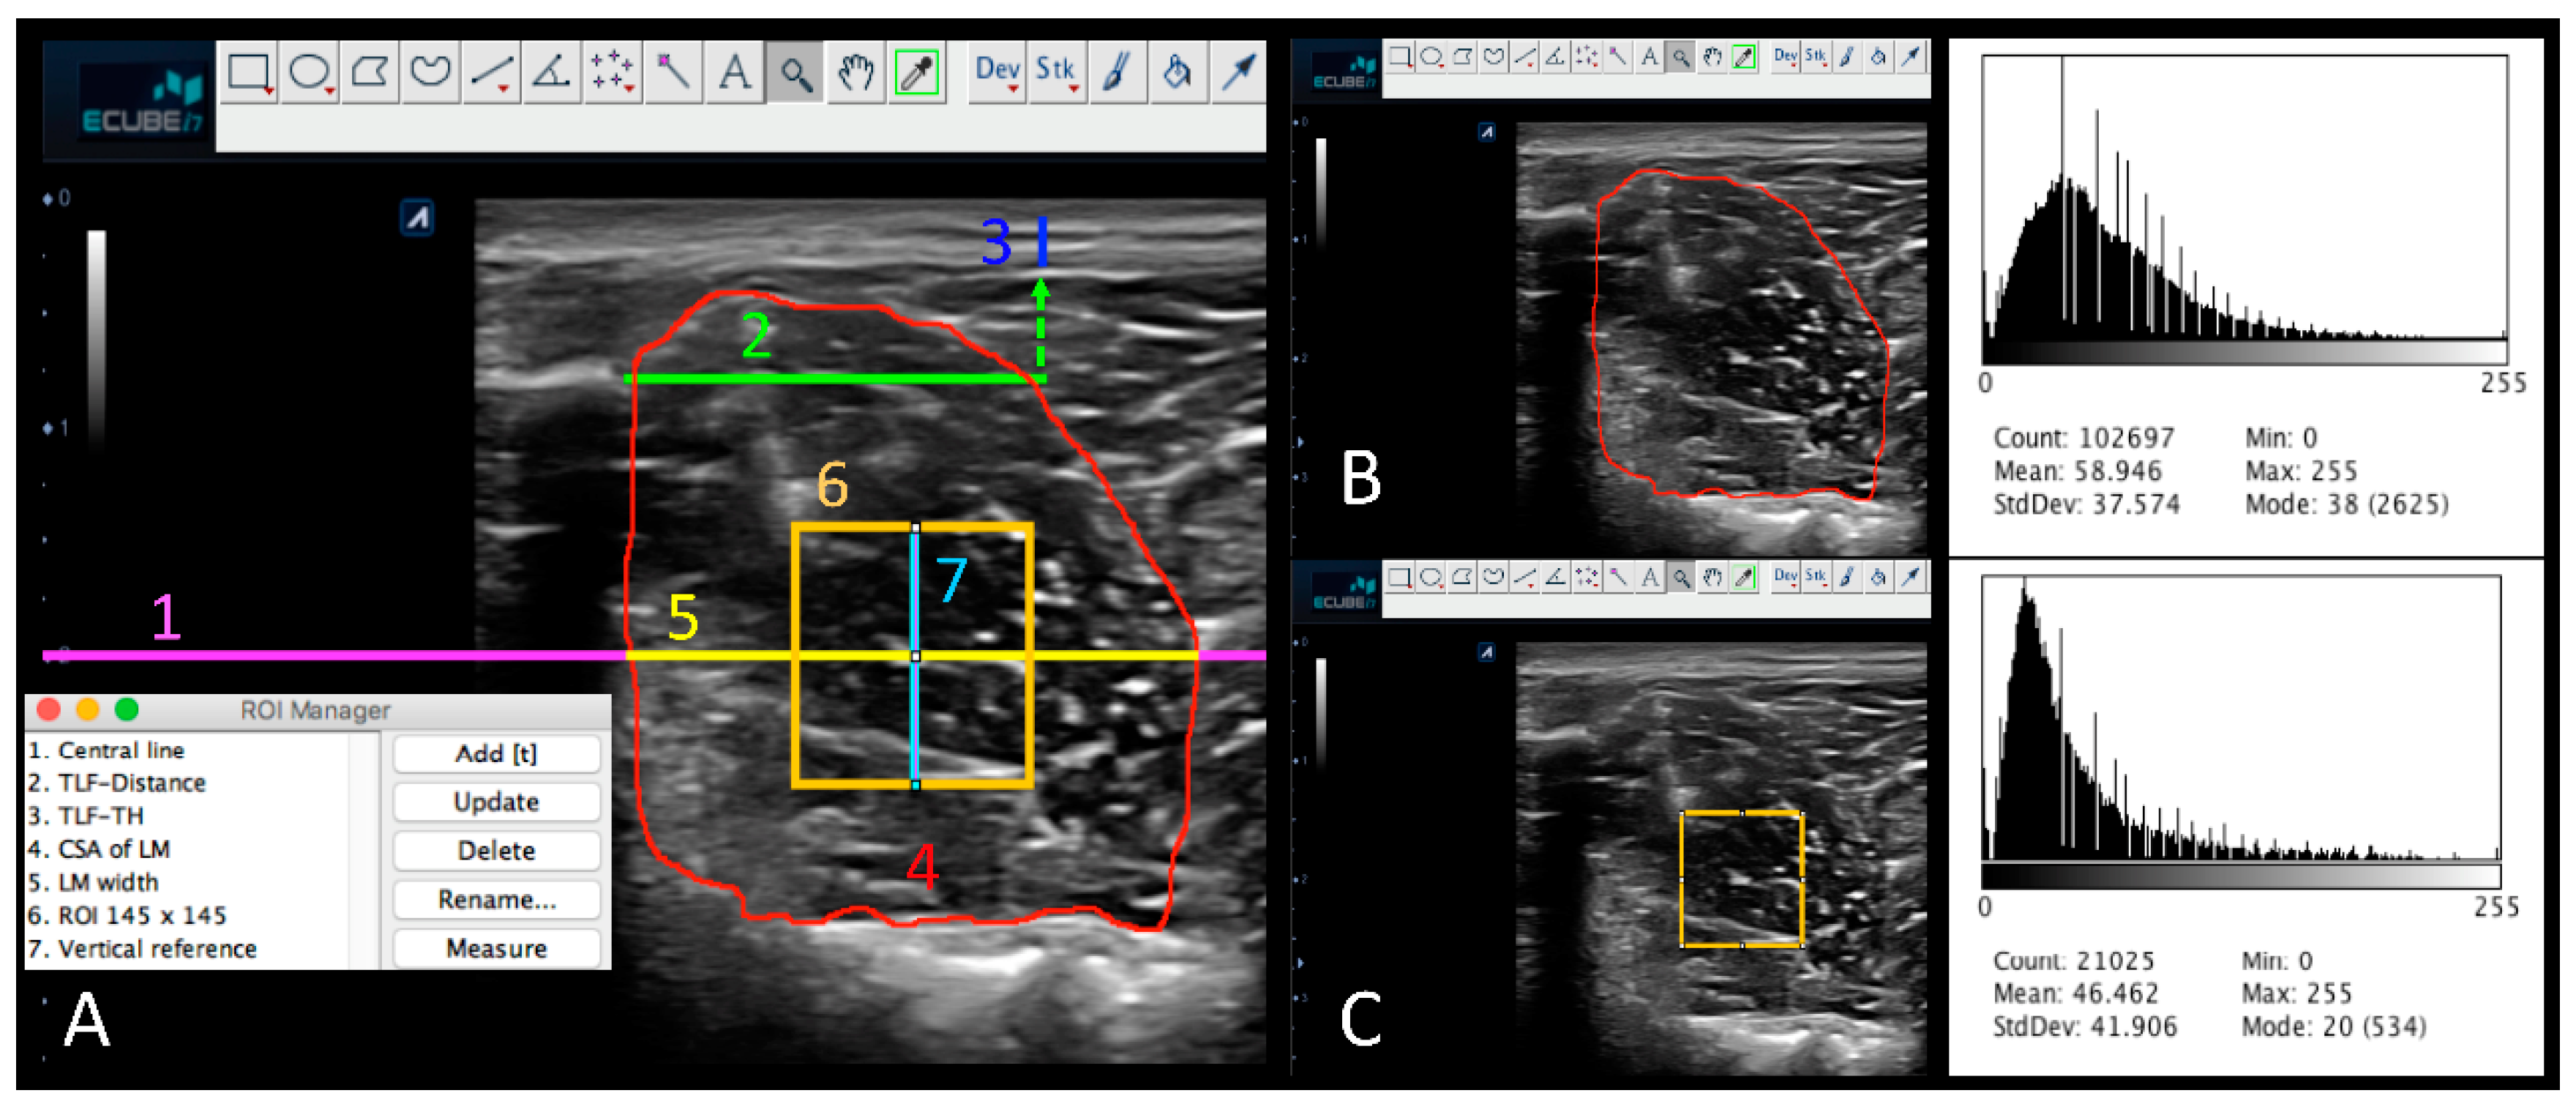

| ImageJ ultrasound imaging protocol for image measurements |

| 1. Image calibration from pixels to cm of LM at resting |

| 2. Activating the ROI manager tool for storing selections |

| 3. Delimitation of the transverse reference line at 2 cm deep |

| 4. Delimitation of the 2 cm transverse line from the L4 spinous process |

| 5. TLF-TH measurements |

| 6. Categorization of TLF-MPH into 4 groups based on the Likert-type scale |

| 7. CSA of LM delimitation and measurements at resting |

| 8. LM-CSA histogram display |

| 9. Delimitation of the LM width line at 2 cm deep |

| 10. ROI generation of 145 × 145 pixels |

| 11. Delimitation of the vertical reference line for ROI adjustment |

| 12. ROI placement at mid-point of LM width and vertical reference line |

| 13. Histogram display of the LM-ROI |

| 14. CSA of LM delimitation and measurement during the CAL test |

| 15. CSA difference of LM during resting and muscle contraction (CSADif.) |